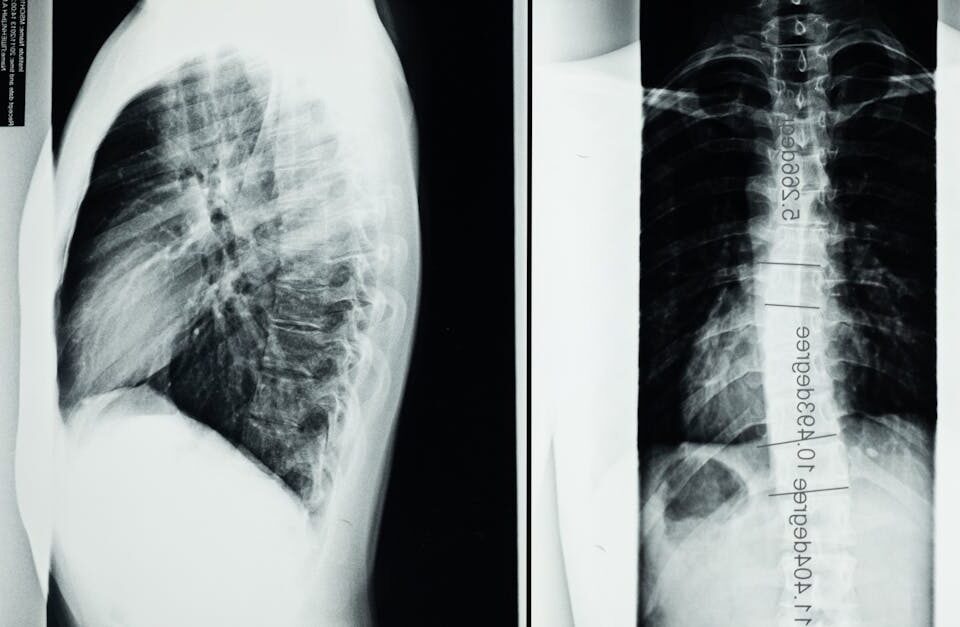

L’arthrose de la colonne vertébrale, qu’elle soit cervicale ou lombaire, est une maladie dégénérative caractérisée par une usure progressive des articulations vertébrales et des disques intervertébraux. Cette dégénérescence discale entraîne des douleurs lombaires fréquentes, une limitation des mouvements, ainsi qu’une raideur cervicale pouvant être invalidante. En particulier, l’arthrose sévère s’accompagne souvent d’un syndrome facettaire, responsable de douleurs intenses liées à l’usure des petites articulations postérieures de la colonne.

Pour mieux comprendre les mécanismes, il est utile de savoir que la dégradation des disques intervertébraux provoque une diminution de leur hauteur et leur élasticité. Cela modifie la posture et l’alignement vertébral, augmentant les contraintes sur les articulations vertébrales et accentuant le syndrome facettaire. La mobilité devient alors restreinte, et des symptômes neurologiques tels que picotements ou engourdissements peuvent apparaître.